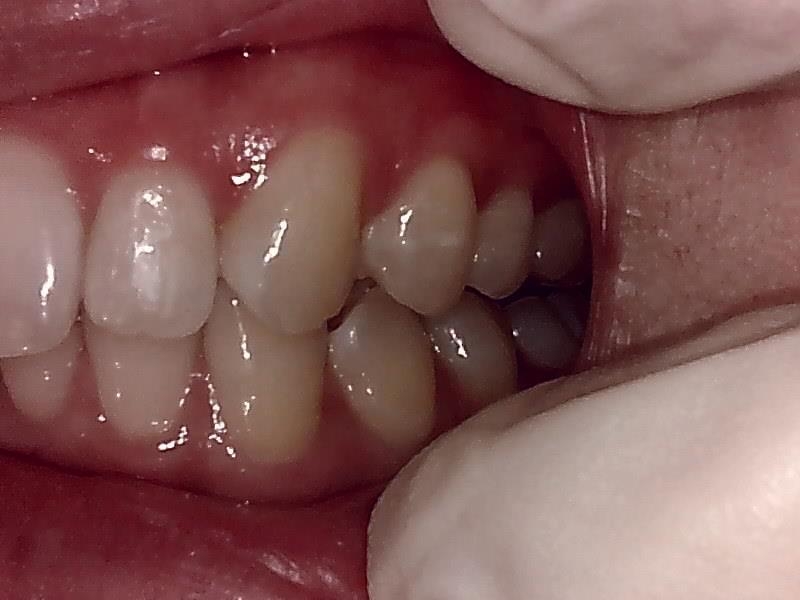

左側